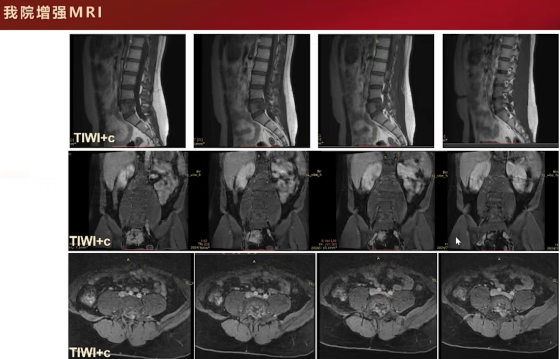

随后的磁共振检查,T2加权像呈高信号,增强扫描可见分隔样环形轻中度强化,这些支持征象提示为软骨源性肿瘤。主要依据包括T2信号较高、膨胀性骨质破坏伴硬化边、内部点状钙化以及增强扫描呈环形和分隔样强化,综合判断为软骨肉瘤。